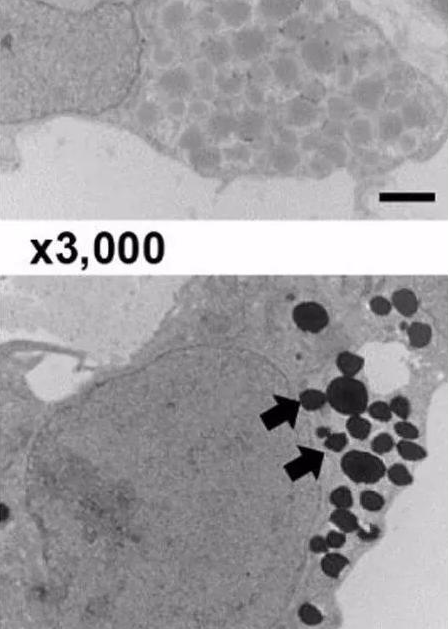

圖. 電鏡下細(xì)胞內(nèi)EPO的分泌囊泡